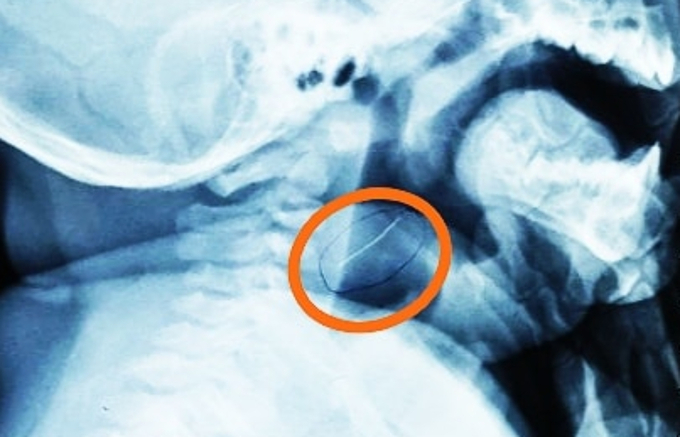

Ăn phải sợi kim loại sắc nhọn dài 2 cm sót trong tô cháo cá, bé trai 8 tháng tuổi bị thủng hạ họng, may cấp cứu kịp thời.

Dị vật gắp ra không phải xương cá mà là một sợi kim loại mảnh, rất cứng và nhọn hai đầu, dài gần 2cm, bác sĩ Trần Thiện Nhơn, khoa Tai Mũi Họng, ngày 29/1 cho biết. Sợi kim loại này đang cắm sâu vào vùng hạ họng bệnh nhi, may mắn là chưa đâm quá sâu nên tính mạng em bé không gặp nguy hiểm.

Sợi kim loại găm sâu vào họng cháu bé trước khi được lấy ra. Ảnh: Bệnh viện cung cấp.